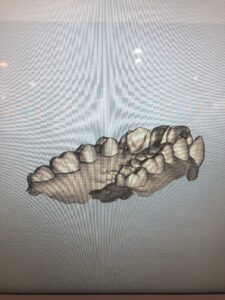

「iTero」で撮影した3Dデータは、このように色々な角度から動かして見ることができるので、自分の歯はこんな形をしているのか!など新発見があるかもしれません。